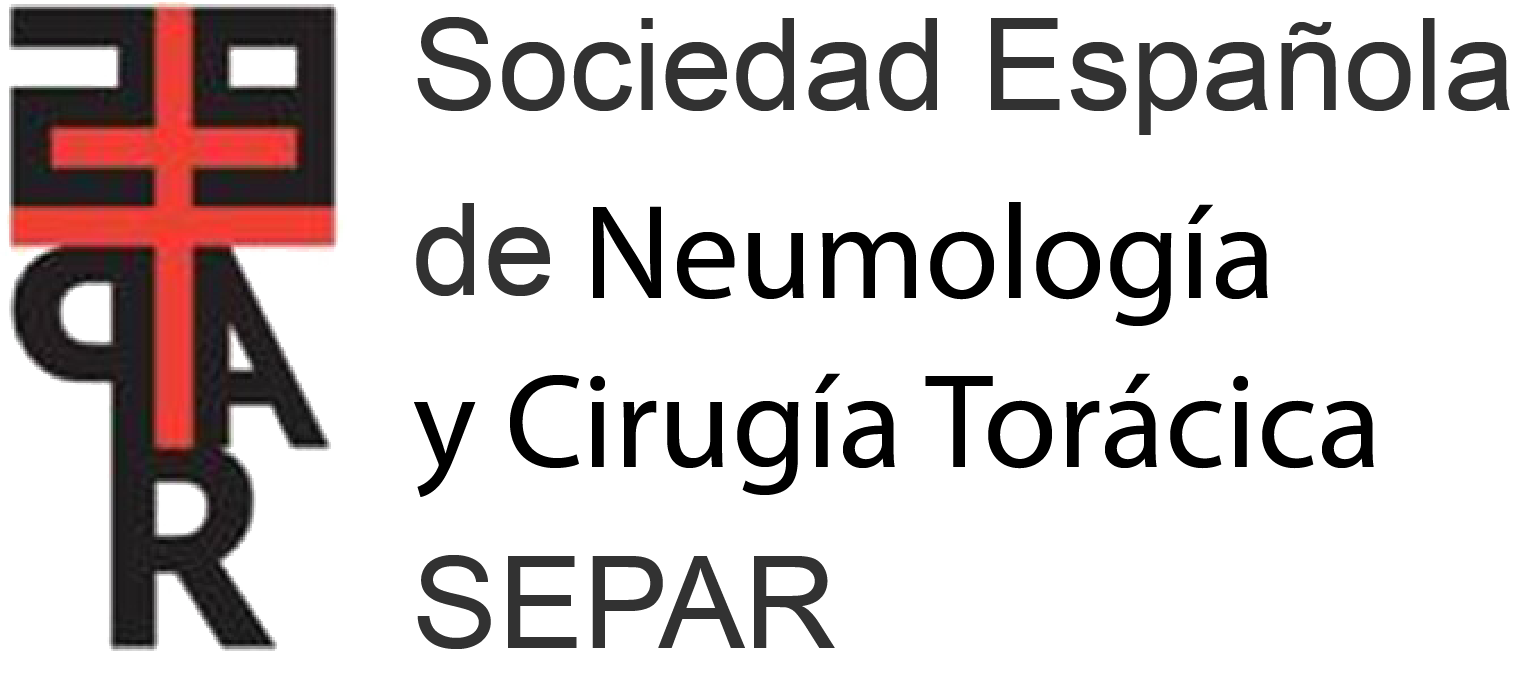

A 22-year-old woman was referred to our emergency radiology unit with sudden onset of shortness of breath and left-sided chest pain. The chest radiography revealed left hilar tubular opacite (arrow) and hyperaeration (asterisk) in the upper zone of the left lung (Fig. 1). The contrast enhanced computed tomography (CT) showed a non-contrast enhancing tubular mass that was seen extending from the left hilum, with surrounding hypoattenuation of the apicoposterior segment of the left upper lobe (asterisk), a finding indicative of hyperinflation (Fig. 2A). There was also no connection between the non-contrast tubular mass (arrows) and pulmonary artery of the apicoposterior segment in the left upper lobe (Fig. 2B–C). CT findings were also including mucocele and occlusion of the bronchus central to the mucocele. CT results (mucocele with hyperaeration of the adjacent lung parenchyma) were considered pathognomonic for bronchial atresia. Surgical treatment was no performed because the patient refused operation.

The reformat coronal CT at maximum inspiration (A) shows a non-contrast enhancing tubular lesion with surrounding hypoattenuation of the apicoposterior segment of the left upper lobe (asterisk), a finding indicative of hyperinflation. The coronal CT scan also demonstrates aerial trapping in the apicoposterior segment of the left upper lobe. The contrast enhanced maximum intensity projection images (B and C) reveal no connection between the non-contrast tubular lesion (arrows) and pulmonary artery of the apicoposterior segment in the left upper lobe.